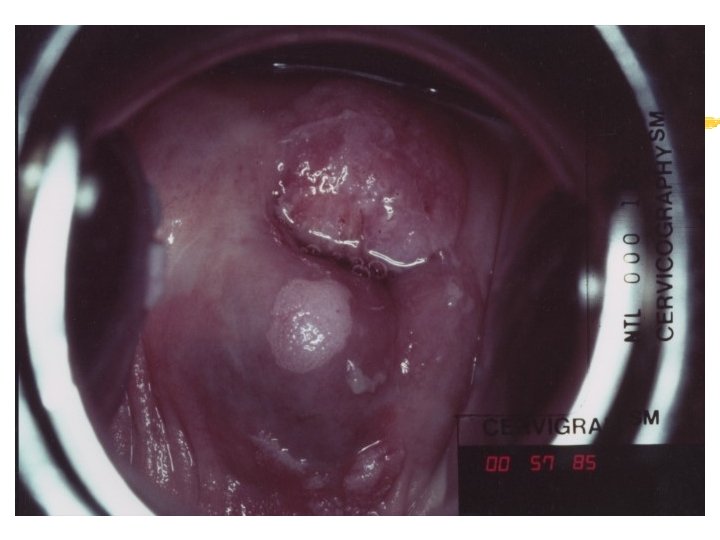

Warning signs of early cervical cancer 1. Yellowish and friable epithelium 2. Abnormal contour 3. Ulceration 4. Atypical vessels 5. Very severe colposcopic atypia 6. Large, significant lesion 7. Canal lesion, going out of range 8. Perimenopausal and post radiation

Mimics of cervical cancer 1. Severe cervicitis e. g. , herpes, syphilis 2. Benign ulceration e. g. , trauma 3. Foreign body reaction 4. Granulomatous cervical conditions 5. Granuloma inguinale 6. Lymphogranuloma venereum 7. Schistosomiasis 8. Cervical condylomata Cololposcopy aids differentiation. Histology is the gold standard

Cervicography: This is NOT Colposcopy High-quality colposcopic-type photography of the cervix Cervicoscope - Hand-held camera with a macrolens and a ring-flash Cervicogram - 35 -mm photo slide is taken Principles Recognition of lesions by means suitable magnification and illumination Fix up the problems of colposcopy 1. a less expensive form 2. noninvasive method 3. do not require expert skill

Procedures of cervicography A) Taking a 35 -mm cervicogram (1) Insert speculum and open as wide as possible … expose an entire cervix and upper vagina (2) Apply first application of 5% acetic acid by dabbing … cleanse the cervix of blood and mucus (3) View the cervix through the cervicoscope … allows time to begin taking epithelial change (4) Apply second application of acetic acid. (5) Take two cervicogram pictures B) Developing the images C) Interpreting a magnified image that was projected on the screen (1) Negative if no definitive lesions are visible (2) Atypical if there was evidence of acetowhite lesion of doubtful significance (3) Positive if there was evidence of a minor or major-grade lesion or cancer